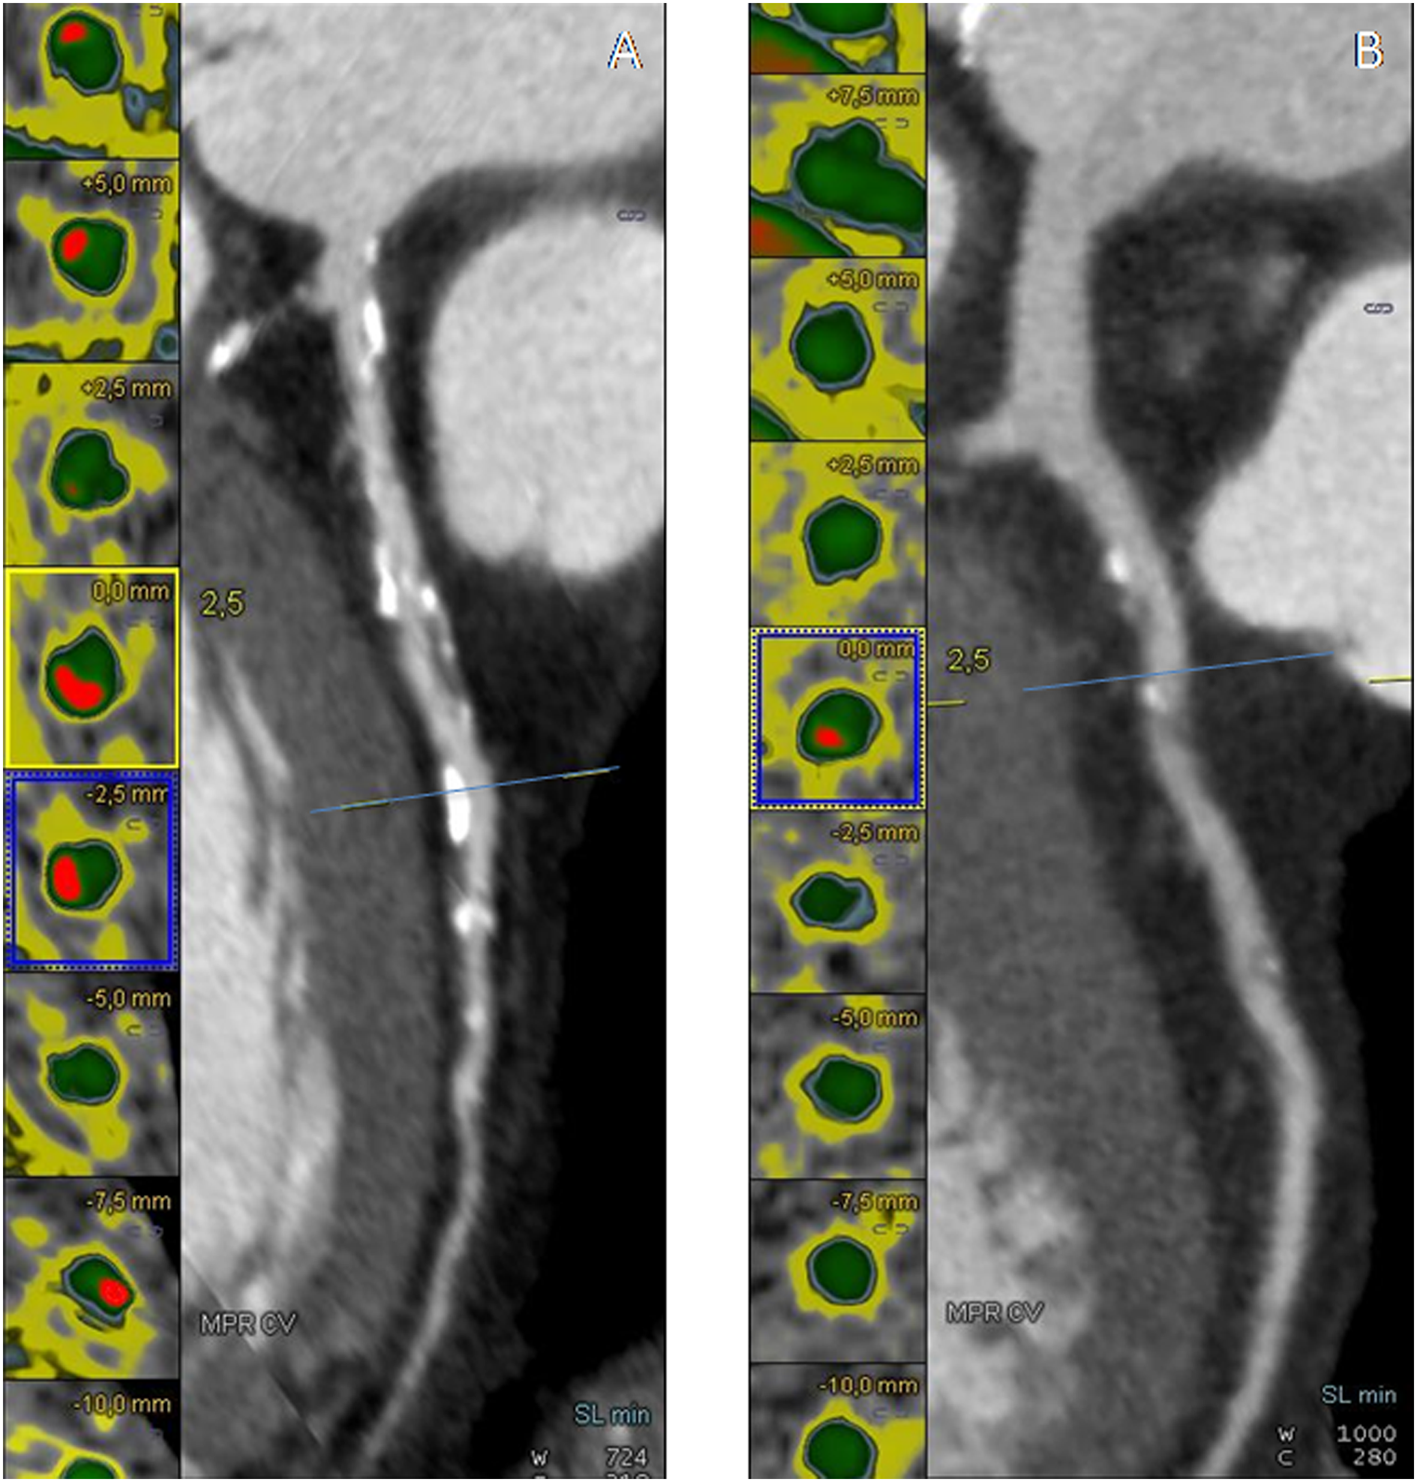

There was significant difference between DM−CAD+ and DM+CAD+ according to NCS and NSP (P = 0.026, P = 0.04, respectively). Cascore was significantly higher in DM+CAD+ compared to DM−CAD+ (Figures 1 and 2): 1,068.7 (517.2–2,086.85) vs 214.05 (72.98–970.15) P = 0.019. As regards plaque characterization, CPV was significantly higher in DM+CAD+ [105.85 (51.2–341.73) mm3] compared to DM−CAD+ [42 (7.2–105.9) mm3] P = 0.014, but there was no significant difference according to NCPV and TPV: 519.85 (411.93–1,064.85) mm3 for DM+CAD+ and 421.85 (240.10–689.58) mm3 for DM−CAD+ P = 0.37 and 688.95 (470.05–1,436) mm3 for DM+CAD+ vs 454.45 (257.78–820.83) mm3 for DM−CAD+ P = 0.16, respectively. RI was 1.40 ± 0.24 for DM+CAD+ and 1 ± 0.19 for DM−CAD+ P < 0.001, and plaque burden was 0.45 ± 0.14 for DM+CAD+ and 0.27 ± 0.15 for DM−CAD+ P < 0.001. Results are summarized in Table 2.

Figure 1. (A,D) Non-contrast enhanced images showing calcium deposits (yellow) on the left descending coronary artery (LAD) in a non-diabetic CAD patient (DM−CAD+) and in a diabetic CAD patient (DM+CAD+), respectively. (B,E) cMPR of LAD is provided for DM−CAD+ and DM+CAD+. (C,F) Plaque characterization: the calcific (yellow) and non-calcific (pink) components of the plaque are highlighted; the vessel lumen is represented in green. DM+CAD+ displayed significantly higher coronary calcium values compared to DM−CAD+.

Figure 2. (A,B) Cross-sectional view and cMPR of the left descending coronary artery (LAD) in a non-diabetic CAD patient (DM−CAD+) and in a diabetic CAD patient (DM+CAD+). In cross-sectional images, the vessel lumen is represented in green whereas the calcific component of the plaque is red.

Calcium score, CPV, plaque burden, and RI were significantly higher in DM+CAD+ compared to DM−CAD+. Previous studied have examined CAD and plaque features in diabetic patients by CTCA. Diabetics showed extensive coronary artery calcium deposits and, therefore, a larger atherosclerotic plaque burden with a consequent higher risk for all-cause mortality than in non-diabetic patients (5, 47–54). Gao et al. (47) found that diabetics compared to non-diabetics have higher total coronary artery calcium, a higher proportion of coronary segments with plaque and multivessel obstructive disease. In a study by Van Werkhoven et al., obstructive CAD and the number of diseased segments, with obstructive and non-obstructive plaques, were higher in diabetics than non-diabetics. Total Agatston score was higher in diabetic patients (440 ± 786 vs 195 ± 404, P < 0.001) (5). Khazai et al. found that segment involvement score, segment stenosis score, and total plaque score were higher in diabetics but there was no significant difference in the number of non-calcified plaque between the two groups (50). In one study by Pundziute et al., diabetics showed more diseased segments and more segments with non-obstructive CAD, but Agatston score was similar between the two groups (54). Furthermore, Chu et al. detected more calcified plaques than mixed or non-calcified plaques in diabetics. Among the different degrees of stenosis, mild narrowing was most common, and no significant difference between non-obstructive stenosis and obstructive stenosis was observed (48). In agreement with the aforementioned works, in our study, DM+CAD+ presented more diseased coronaries in terms of coronary calcium, significant stenoses, atherosclerotic burden, and extent of disease. Furthermore, we have quantified RI in diabetic patients by CTCA providing an additional prognostic value comparable only to invasive procedures such as intravascular ultrasound (55, 56). A recent study analyzed CAD features comparing hypertensive, dyslipidemic, and diabetic patients by CTCA reporting the prevalence of positive remodeling as a qualitative parameter (57).